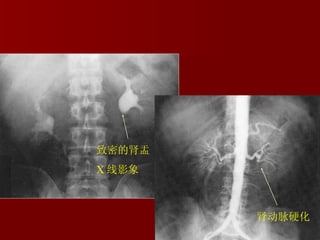

The kidney The long-term renal damage produced by glomerular hypertension probably accountd for progressive glomerulosclerosis in essential hypertension.

Atheromatous renal vascular disease much more commonly causes renal impairment in elderly hypertensive subjects than younger patients with treated mild to moderate hypertension.

肾动脉硬化 肾动脉硬化 致密的肾盂 X 线影象